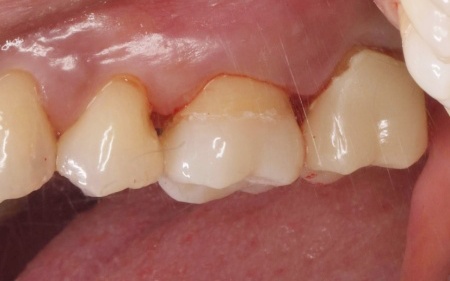

40代女性 金属アレルギーを発症した患者様のメタルインレーを除去し非金属の素材で修復した症例

そこで詰め物の素材には、自費診療の白い素材「セラミック」の中でも、人工ダイヤモンドと呼ばれるほど強度があり、審美性にも優れている「ジルコニア」を選択しました。

そのため、噛み合わせが強くかかる歯のみジルコニアで作製し、ほかの歯は強度の面でジルコニアには劣るものの、保険診療で非金属の白い素材「CAD/CAM冠」で作製することを提案し、同意いただきました。

まずはメタルインレーをすべて外し、詰め物を装着するために歯の形を整え、型取りを行います。

後日、完成した詰め物を装着し、歯にぴったりと合っているか、噛み合わせに問題がないかを十分に確認して、治療を終了しました。